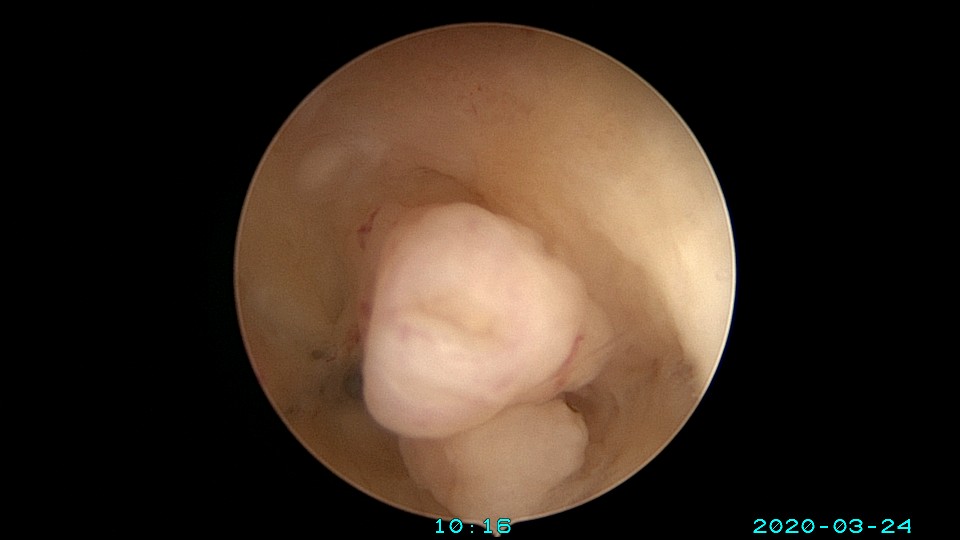

患者65岁,G1P1,顺产1次。安环30年,绝经10年。外阴白斑,阴道明显萎缩,无法置入扩阴器,阴道内镜方式找到宫颈外口,宫颈萎缩,穹隆几乎消失,无法夹持宫颈,宫颈管见多个息肉,宫颈内口狭窄坚硬,难以扩张。微型异物钳探查宫腔方向,用异物钳、微型剪刀扩大宫颈内口失败,改用双极电针切开宫颈内口,但镜子仍无法进入宫腔。用异物钳反复牵拉O型环至阴道内,中弯钳配合卵圆钳拉出节育环,环变形。有人问我何不用取环钩取环,这个病人探针和取环钩都无法发挥作用。